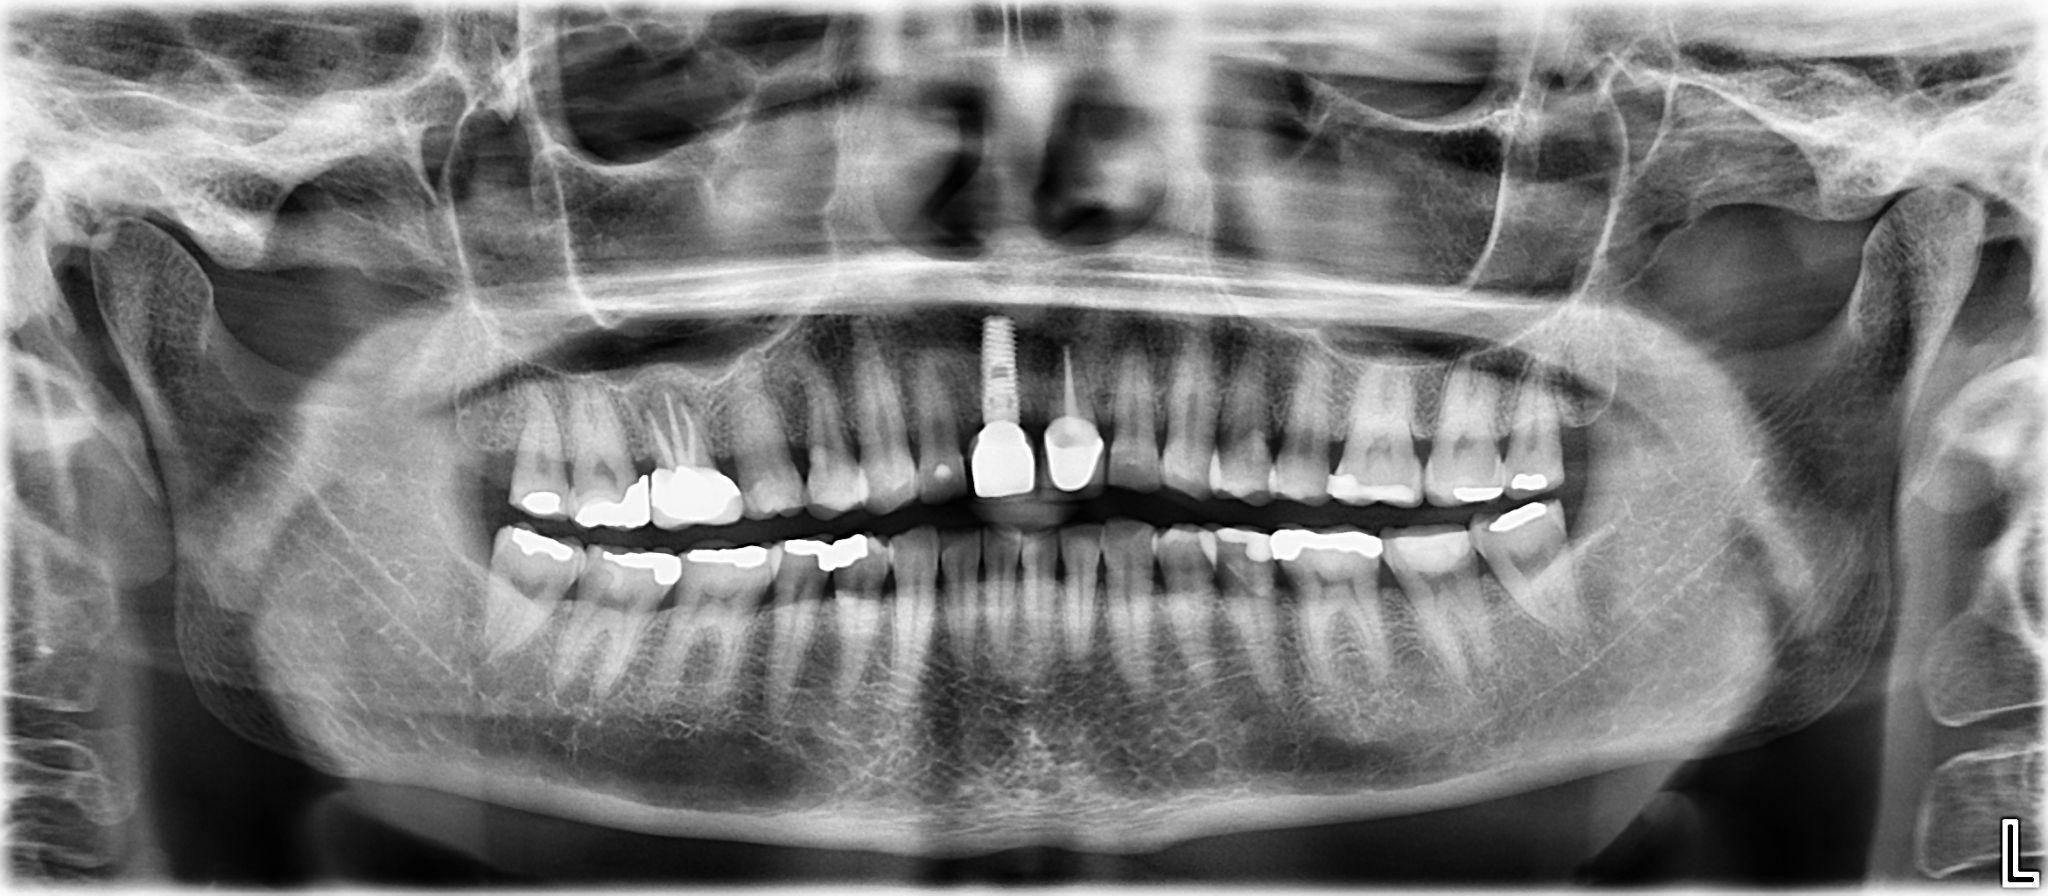

5 / 25

5. What option cannot be selected for the first quadrant of this panoramic X ray?

6 / 25

6. What option cannot be selected for the third quadrant of this panoramic X ray?

7 / 25

7. What option cannot be selected for the forth quadrant of this panoramic X ray?

8 / 25

8. What option cannot be selected for the upper jaw of this panoramic X ray?

9 / 25

9. What option cannot be selected for the lower jaw of this panoramic X ray?